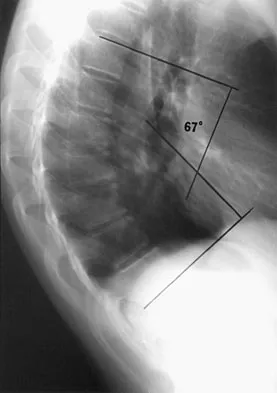

Examination of a 13-year-old boy with asymptomatic poor posture reveals increased thoracic kyphosis that is fairly rigid and accentuates during forward bending. The neurologic examination is normal. Spinal radiographs show 10 degrees of scoliosis at Risser stage 2, and there is no evidence of spondylolisthesis. A standing lateral view of the thoracic spine is shown in Figure 41. The kyphosis corrects to 50 degrees. Management should consist of

Explanation